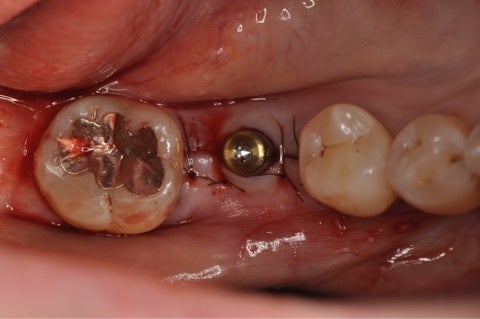

それでは当院でのインプラント手術の例です。

患者様は左下の奥歯が欠損してしまい、しっかり食事を摂りたいという希望で無痛治療でのインプラント手術を選択されました。

術前に綿密にシミュレーションを行っていたものとほぼ同じ位置に埋入されていることが確認できます。

今回は術後の痛みや腫れが殆ど無かったとのことで患者様には大変喜んで頂き、歯が入ることを楽しみにされています。

今後はこの歯茎から見えるインプラントに歯の形を作成していきます。